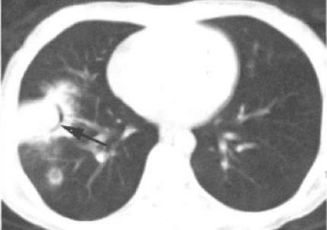

例1:患者长期口服免疫抑制剂,近期发热,痰中带血

图1 胸部CT

图1 胸部CT诊断:IPA。

空气新月征是曲霉菌的典型CT。当然,只说一个空气新月征,那也太枯燥了,不能满足大家的胃口。